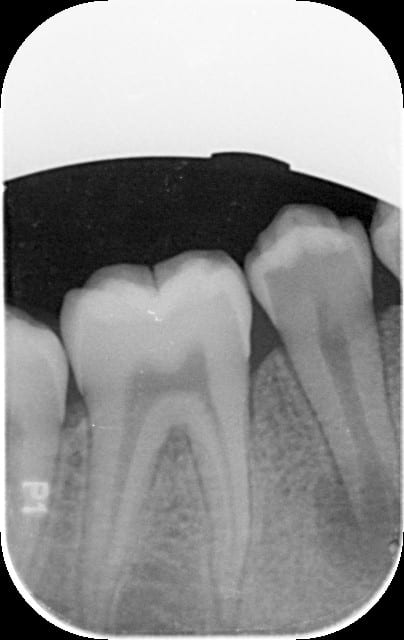

je prends une radio voir ci jointe et la c est la drame... un kyste sur la racine non edifiée!!! il n y a jamais eu de soucis particulier selon les dires de la maman et je remarque sur gencive une trace d une ancienne infection en regard de la zone kystique .

Par principe, une radio sous une autre incidence, ou une pano, serait de bon aloi, afin d'éliminer une superposition du trou mentonnier.

L'image paraît mal centrée par rapport à l'apex en fait, ça me gêne.

Voir également le décalage d'édification radiculaire par rapport à 35.

d'après la radio la dentine de la 45 est largement plus radioclaire que sur la 46. Est-ce que cette radioclarté est liée à une carie ou à un manque de minéralisation de la dentine ou les 2... Mais même si l'émail a l'air intact il a pu y avoir une contamination bactérienne peut-être par le fond du sillon occlusal.

La 5 présente une malformation, que tu vois à la radiographie (au niveau le plus médian et le plus occlusal). Cela fait une sorte de dens in dente toute petite, mais qui laisse pénétrer les bactéries dans l'endodonte.